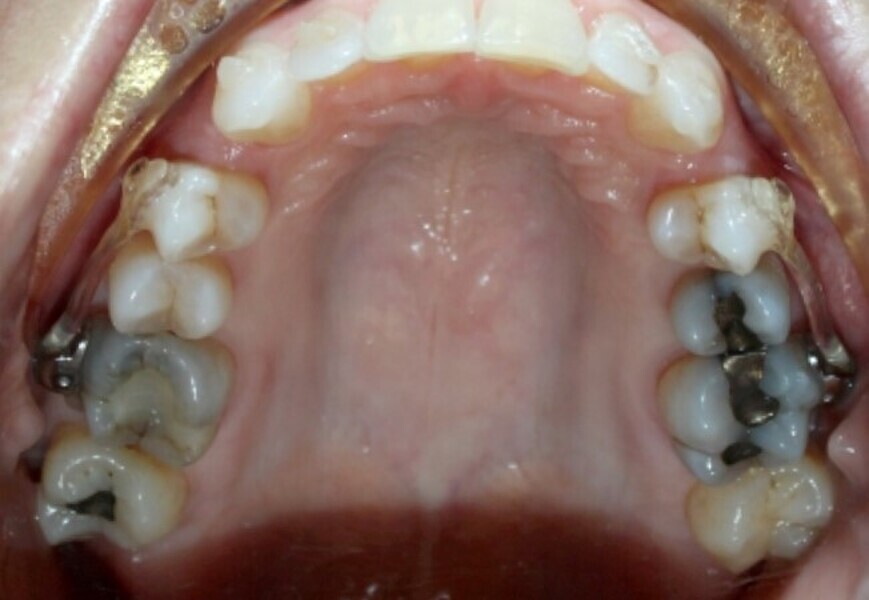

Fig. 20a: Class III malocclusion requiring fixed appliance treatment. (a) Frontal view. (b) Occlusal view.

Fig. 20b: Class III malocclusion requiring fixed appliance treatment. (a) Frontal view. (b) Occlusal view.